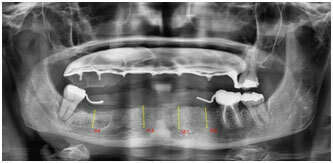

Fixation d’une prothèse par une barre sur 4 implants